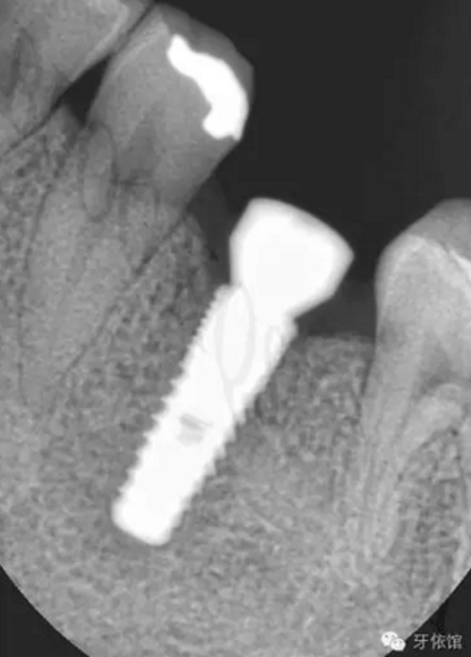

再將烤瓷冠就位,拍X光片,檢查烤瓷牙與基臺之間是否密貼。

但是由于微創(chuàng)種植一般都不切開翻瓣,出血少,疼痛輕,無腫脹,患者較容易接受。所以如果條件允許,您不妨可以 找一個簡單的病例試一試。在手術(shù)之前,必須要對病例進行詳細的分析,周密的計劃。如果我們術(shù)前對種植區(qū)域牙槽骨沒有進行充分的分析就盲目的操作,就可能會出現(xiàn)一側(cè)牙槽骨剩余量不足1mm的情況,導(dǎo)致種植后種植體脫落,或一側(cè)植體達骨面以下,而另一側(cè)卻有螺紋暴露。

如下圖所示從外觀上來看,擴孔的位置位于牙槽嵴頂?shù)闹醒氩课唬穷a舌側(cè)粘膜及粘膜下組織厚度不一,會造成我們判斷有誤。